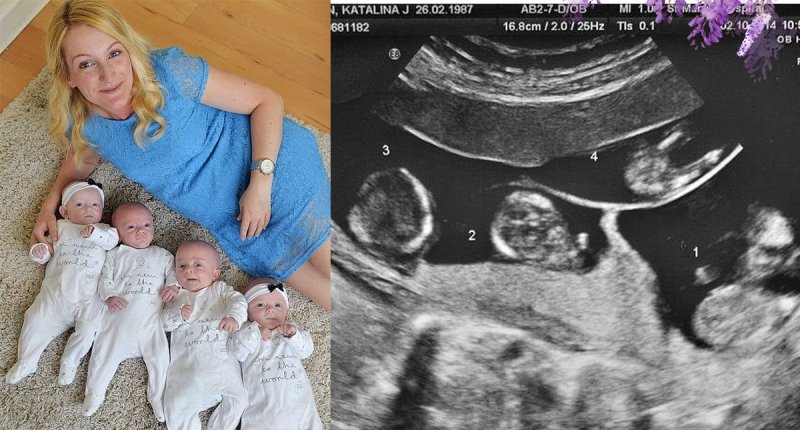

但這個英國婦女卻生下異卵的四胞胎,

這個媽媽名叫馬丁,她患有多囊性卵巢症,

被醫生宣告不孕,但沒想到竟懷上奇蹟般的異卵四胞胎,

異卵四胞胎的機率是70萬分之一,

四胞胎在28周時就被產下,現在四個都十分健康!